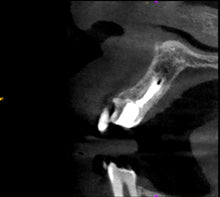

One-Fil PT is based on Tricalcium silicate compounds composition, which requires the presence of water to set and harden.

This material is premixed and is ideal for open apices, vital pulp therapy, perforation repair, apical microsurgery and coronal sealing of the root canal system.